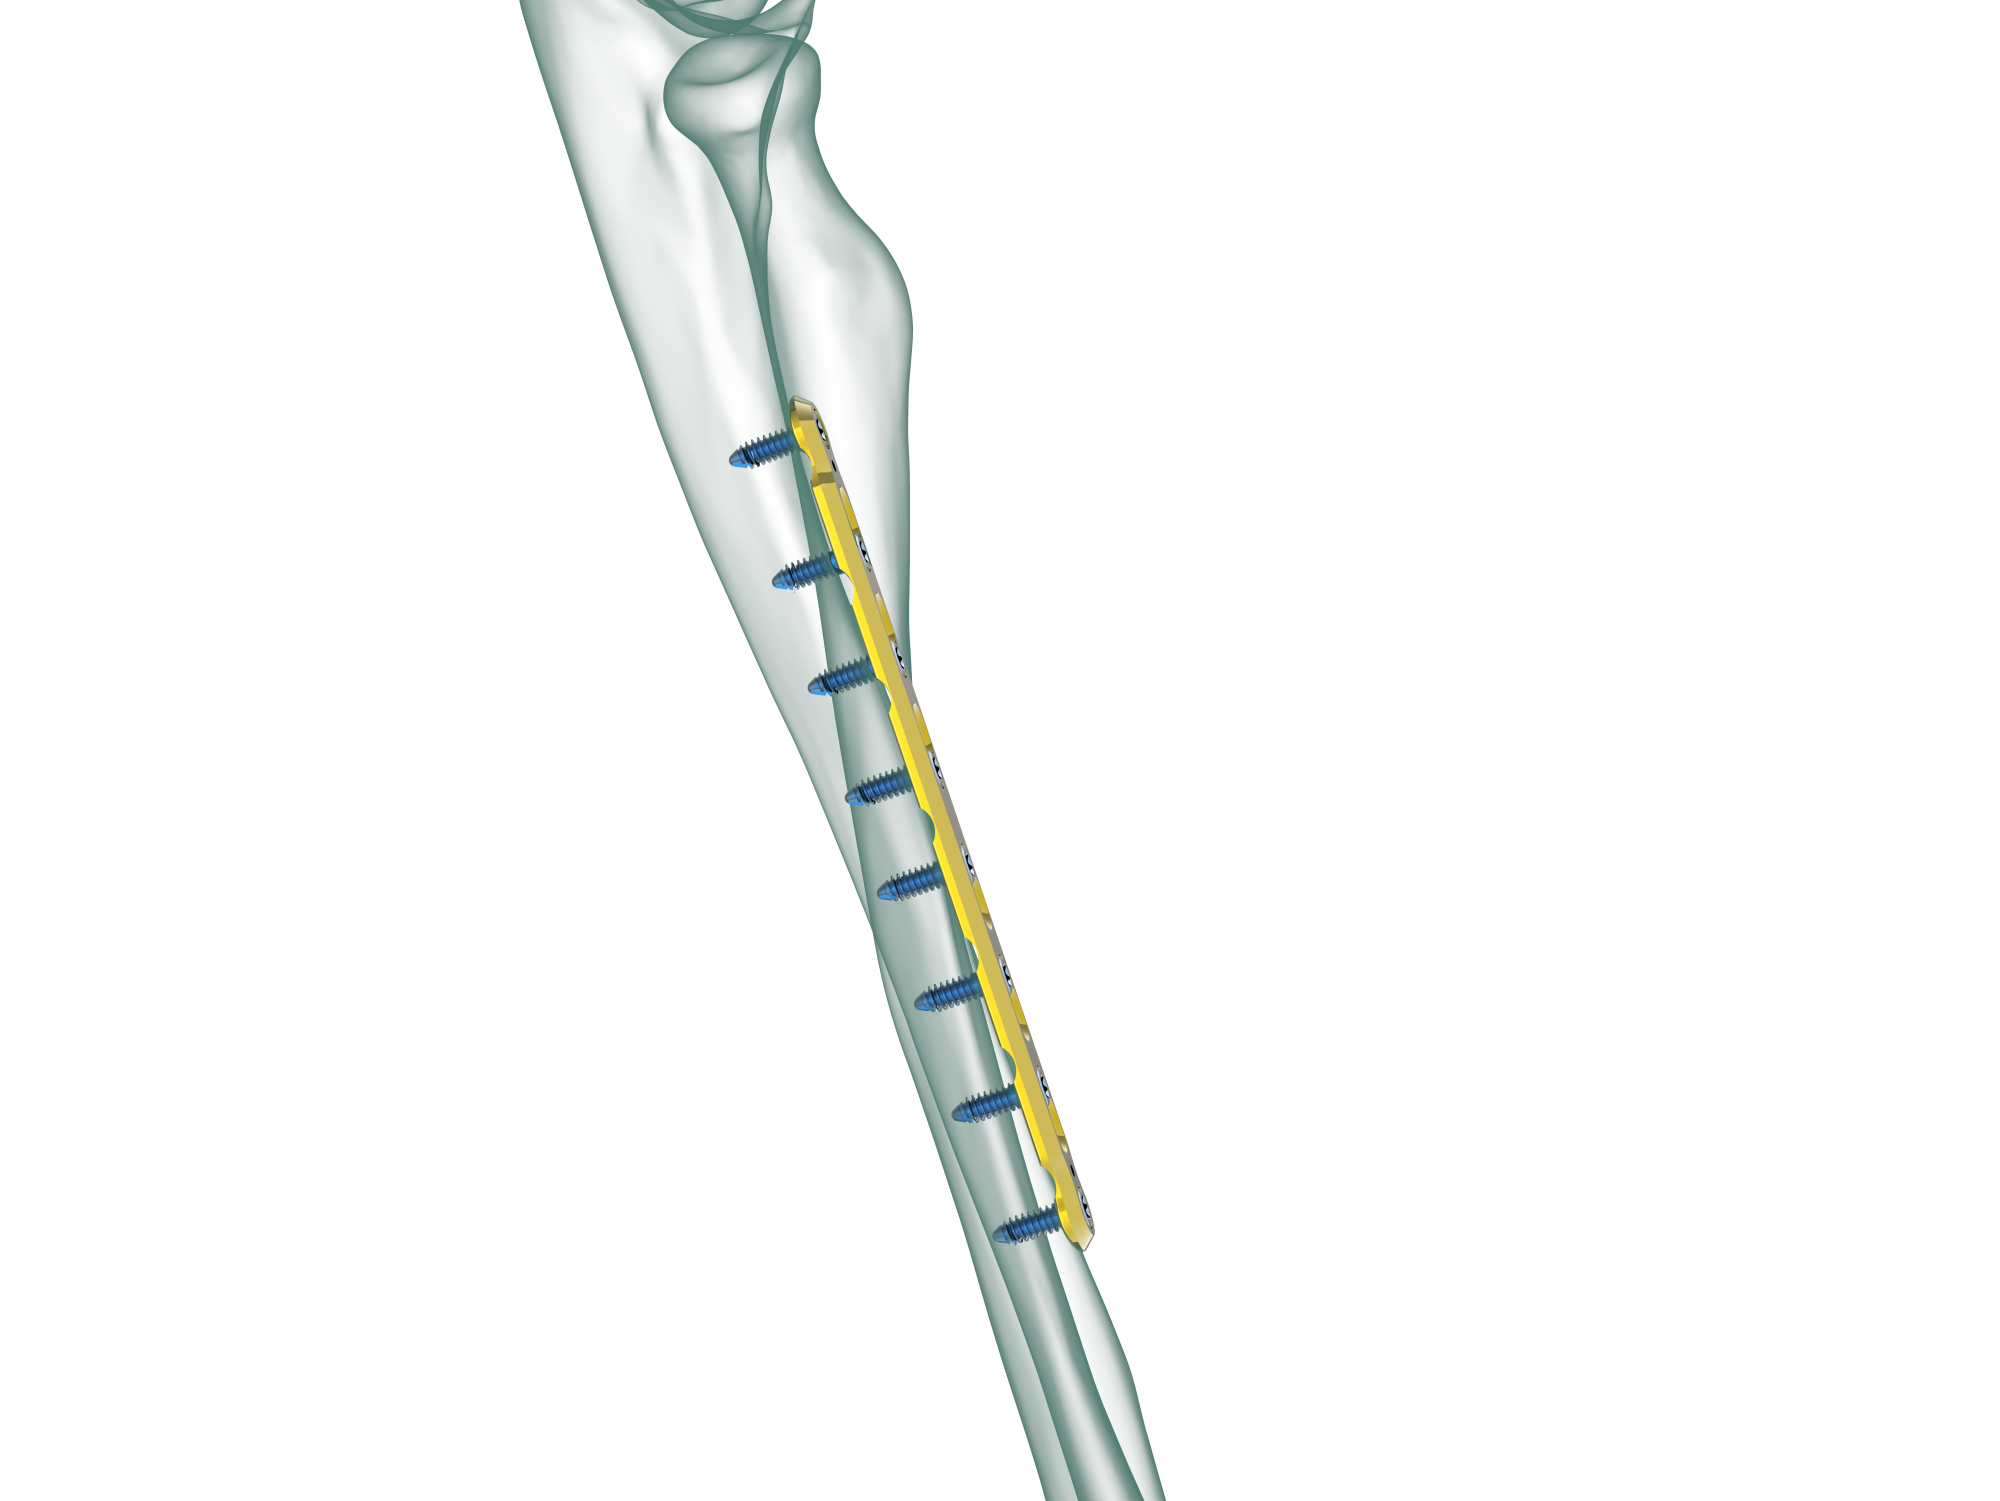

TRUE LOCK 3.5mm Ulna Radius Plate

TRUE LOCK 3.5mm Ulna Radius Plates are indicated for fractures of ulna, radius and fibula shaft.

Radius and ulna body fractures differ from other diaphyseal fractures due to the relationship between both bones and the fractures can affect the elbow and wrist joints. In adulthood, forearm fractures often require surgical treatment, as they are noticeably displaced and unstable.

TRUE LOCK 3.5mm Ulna Radius Plates are made of Ti6Al4V ELI material (ASTM F136)

Low plate-and-screw profile and rounded plate edges minimize potential for tendon and soft tissue irritation.

Kirschner wire holes accept Kirschner wires (up to 1.5 mm) to temporarily fix the plate to the bone , to temporarily reduce articular fragments, and to confirm the location of the plate, relative to the bone.

Locking the screw into the plate does not generate additional compression. Therefore, the periosteum will be protected and the blood supply to the bone preserved.

The combi-hole pro- vides flexibility of axial compression and locking capability throughout the length of the plate shaft.